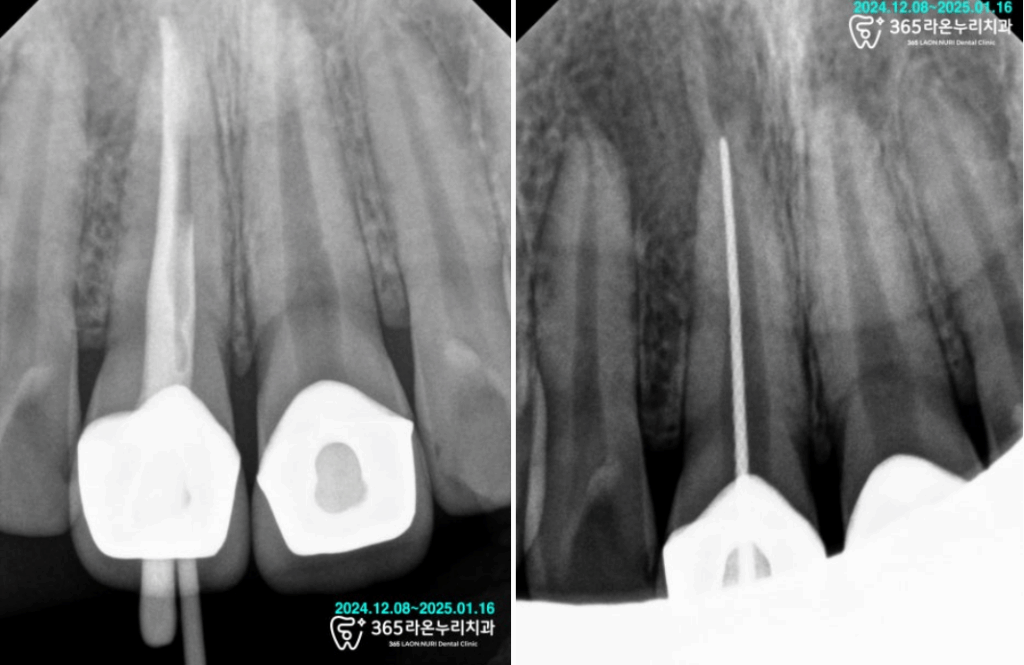

그리고 나서 기존 보철에 구멍을

뚫고 신경치료 과정을 진행하게 되었습니다.

현재는 치아 뿌리 끝에 염증이 많이 있던 상태라,

근관(신경관) 소독 과정을 여러번 진행해주었습니다.

신경치료 과정을 마친 다음,

크라운을 올릴 수 있는 모양으로

치아를 깔끔하게 다듬어드릴 차례입니다.

그렇게 프렙을 거쳐 치아를 깔끔하게

다듬어드린 다음 코어를 채웠습니다.

그다음, PMMA 임시 치아 제작을 위한

스캔을 진행한 뒤 인상 채득을 마쳤습니다.

그리고 나서 인접치아에 있던

충치를 제거한 다음 임시 치아를

세팅한 모습입니다.

최종 크라운이 완성되기 전까지

앞니의 역할을 대신 수행해줄

임시 치아가 잘 제작되었습니다.